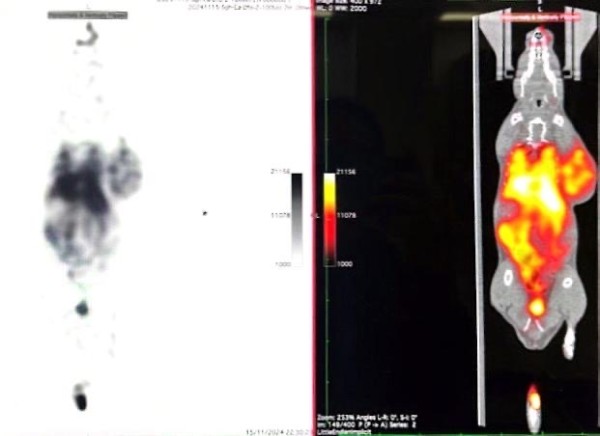

图4:配套诊断药用于小鼠活体 PET/CT 成像(时间点:静脉注射后 2h)